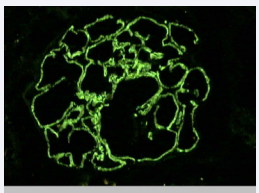

Laboratory tests revealed eosinophilia (22%). In March 2009 the patient underwent a new endoscopic control with repeated small gut biopsies confirming the diagnosis of EG. Successively the disease became corticosteroid-dependent. In May 2013 at age of 43 the patient was referred to the Nephrology Unit for nephrotic syndrome. In January 2014, he noticed progressive oedema in the lower limbs with mild asthenia. Physical examination confirmed the presence of oedema localized in the ankles. Laboratory investigation demonstrated a normal serum creatinine level of 0.8 mg/dl; creatinine clearance was 119 ml/ min, total serum proteins 4.7 g/dl, serum albumin level of 2.9 g/dl. Urine analysis showed proteinuria without haematuria or leukocyturia. Complement levels (C3, C4), white blood cell count, red blood count, hematocrit and platelet count were normal. Anti-nuclear antibodies, cryoglobulins, HCV Ab, HBsAg and tumor markers resulted negative. Immunofixation revealed no monoclonal gammopathy. Urine immunoelectrophoresis showed non-selective proteinuria. Lymphoproliferative disorders were excluded. Renal ultrasound examination demonstrated bilateral normal size, with no abnormalities of the renal parenchyma. The patient underwent a real-time ultrasound-guided left kidney biopsy. Light microscopy showed 25 normal sized glomeruli with very slight diffuse thickening of the capillary walls and slight segmental increase of the mesangial matrix. No significant tubular interstitial or vascular lesions were present except for tubular hyaline droplets. Immunofluorescence study showed the presence of diffuse, finely granular deposits of IgG along the peripheral capillary loops (Figure. 2).

Immunofluorescence microscopy showing a glomerulus with diffuse finely granular peripheral capillary loop deposits of IgG. (X400).

Figure 2: Immunofluorescence microscopy showing a glomerulus with diffuse finely granular peripheral capillary loop deposits of IgG. (X400).

Electron microscopy confirmed the presence of numerous electron-dense deposits on the subepithelial side of the basement membrane. A diagnosis of stage I membranous nephropathy was made.